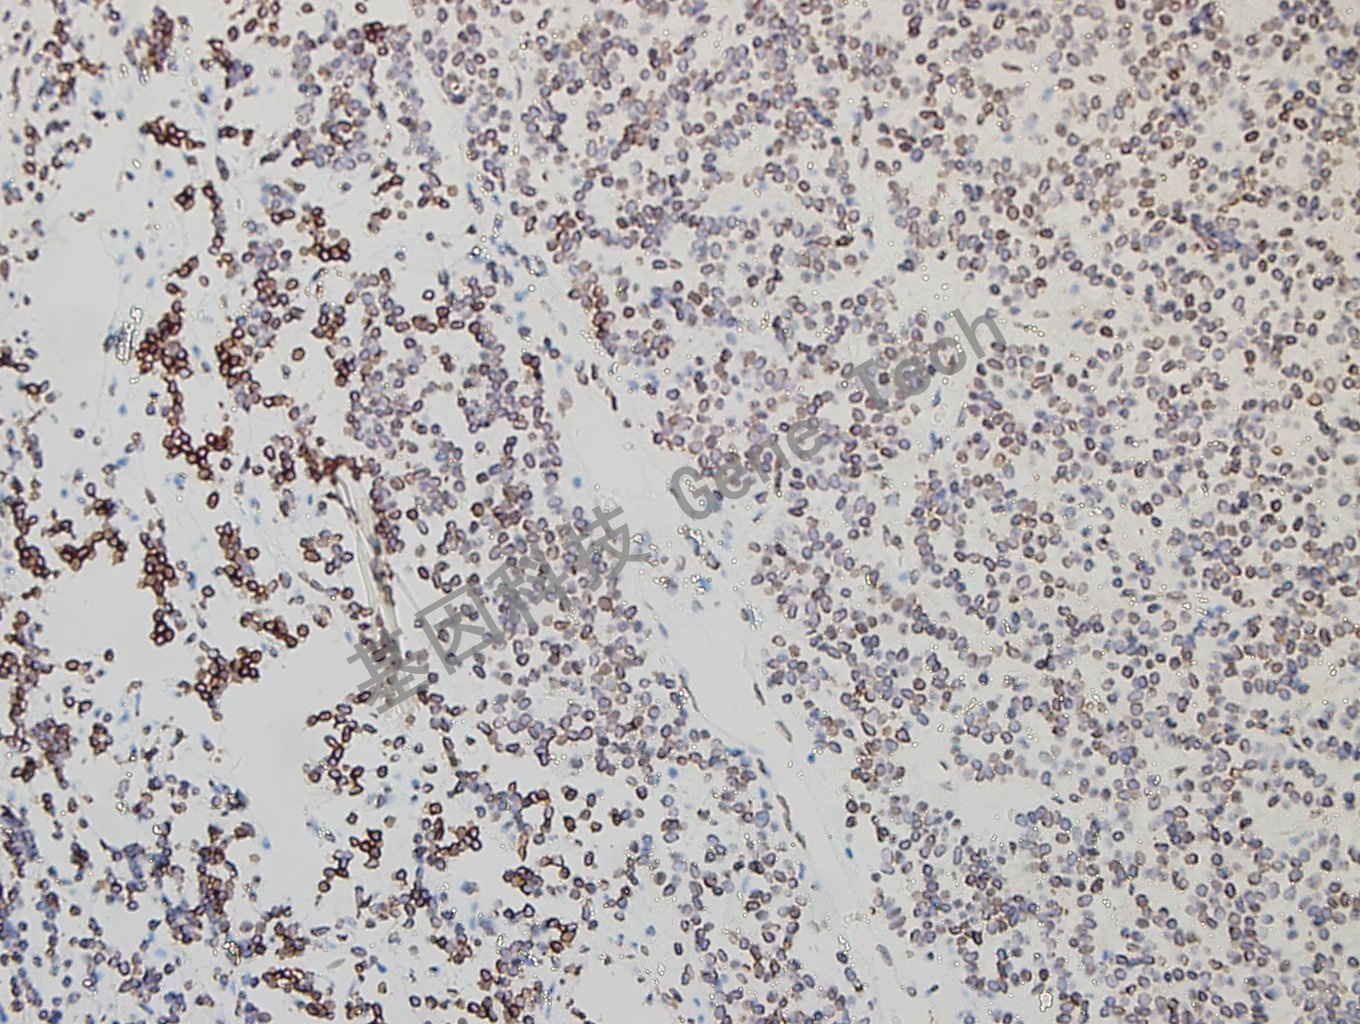

垂体腺瘤石蜡切片,用 GATA2(GT2320)染色,细胞核阳性,DAB 显色。